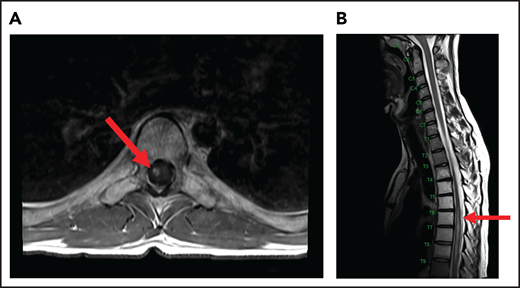

A 24-year-old man presented with stage IVB DLBCL and completed 6 cycles of R-CHOP, with FDG-PET after treatment showing resolution of all disease except in the mediastinum. After a biopsy of this residual FDG+-confirmed DLBCL, he received treatment with salvage chemotherapy with minimal response, followed by mediastinal involved field radiation therapy (IFRT) to a dose of 40 Gy plus a 6-Gy boost, after which he had a CR. Subsequently, he underwent autologous SCT followed by RIC allogeneic SCT. He remained in CR for 16 months, at which time he presented with 3 weeks of new right leg weakness, erectile dysfunction, and urinary hesitancy. The results of a brain MRI were unremarkable, but a spine MRI demonstrated spinal cord expansion and edema with multifocal enhancement within the prior radiation therapy portal from T5 to T9, demarcated by fatty marrow replacement between the T5 and T9 vertebral bodies (Figure 4). A diagnostic evaluation, including CSF analysis, was negative for malignancy, infection, autoimmune or inflammatory conditions, or demyelination. He was diagnosed with radiation-induced myelitis. He was treated with HD-MTX and had a minimal response. Treatment with bevacizumab led to complete resolution of the lesion, and after intensive physical therapy, he regained neurologic function.

MRI of the cervical and thoracic spine of a patient with radiation-induced myelopathy. (A) Axial T1-weighted image after gadolinium contrast shows enhancement within the spinal cord. (B) Sagittal T2 image shows a signal change throughout the patient’s prior radiation portal from T5 to T9, demarcated by fatty marrow replacement between the T5 and T9 vertebral bodies.

Radiation

Ionizing radiation to the brain or spinal cord can cause acute, subacute, or delayed adverse effects.58 Acute brain toxicity from radiation is typically related to cerebral edema and/or raised intracranial pressure and resolves with corticosteroids. Subacute effects caused by radiation-induced necrosis occur weeks to months after radiation and usually present with headache, lethargy, and focal neurologic deficits. Rarely, radiation myelopathy can result from focal radiation delivered to the mediastinum for HL and NHL, as in case 5.61 Spine MRI typically shows contrast enhancement within the spinal cord, and symptoms may resolve with corticosteroids. Bevacizumab has been used to treat radiation necrosis, as described in our case.62 Delayed neurotoxicity typically presents years after treatment. It can present as radiation-induced vasculopathy resulting in strokes or hemorrhage, or as brain atrophy and leukoencephalopathy. Older age and concurrent use of HD-MTX increase this risk.63